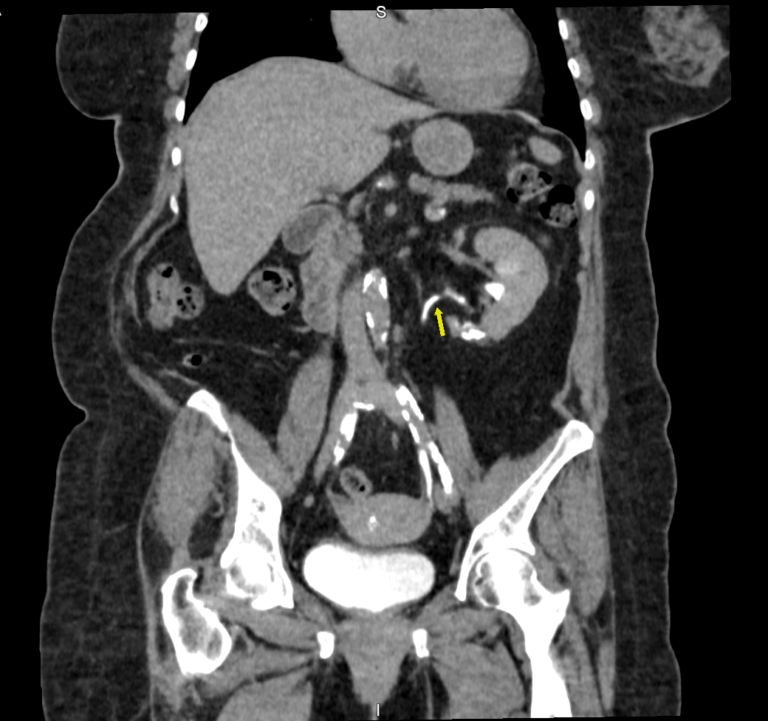

O exame permite avaliar as vias urinárias, sendo possível estudar os dutos que transportam a urina produzida pelos rins até a bexiga, para ser eliminada.

Na urotomografia o uso do contraste é obrigatório. A solução de contraste iodado é administrada por via endovenosa e distribui o contraste entre as estruturas com fluxos sanguíneos, realçando as estruturas hipervascularizadas, mostrando, por exemplo, tumores ou processos inflamatórios.